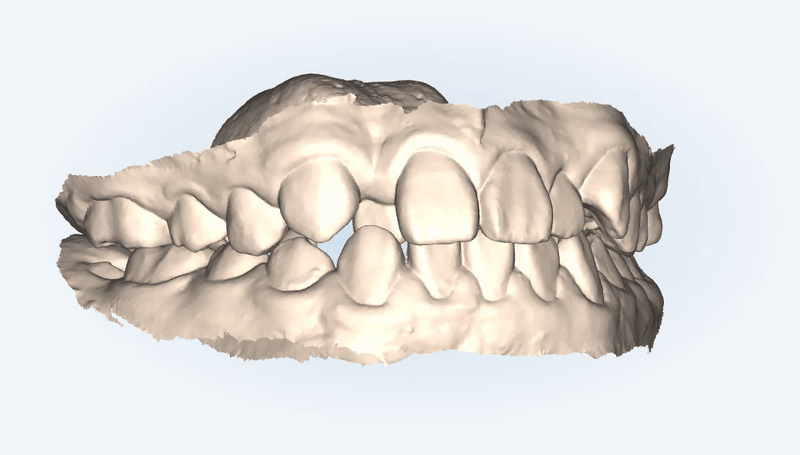

삐뚤빼뚤했던 치아들을

발치 하지 않고 가지런히 할 수 있었던 인비절라인의 특징은 무엇일까요?

바로 '악궁확장' 기능을 통해

앞니와 어금니 모두 제 위치를 찾으며 올바르게 배열되었습니다.

교정 전에는 교합면끼리 이은 선이 안쪽으로, 혹은 바깥쪽으로

뻐드러져 있었는데요.

특수강화 플라스틱 재질인 인비절라인은

치아를 안쪽과 바깥쪽에서 적은 힘으로 지속적으로

잡아주기 때문에

적은 통증으로 악궁을 확장시켜

치아이동을 수월하게 도와줍니다.

환자분께서는 아래 앞니가 3개인 결손치 상태로

정중선을

앞니 3개의 중간으로 최대한 맞춰드리려고 했습니다 :)